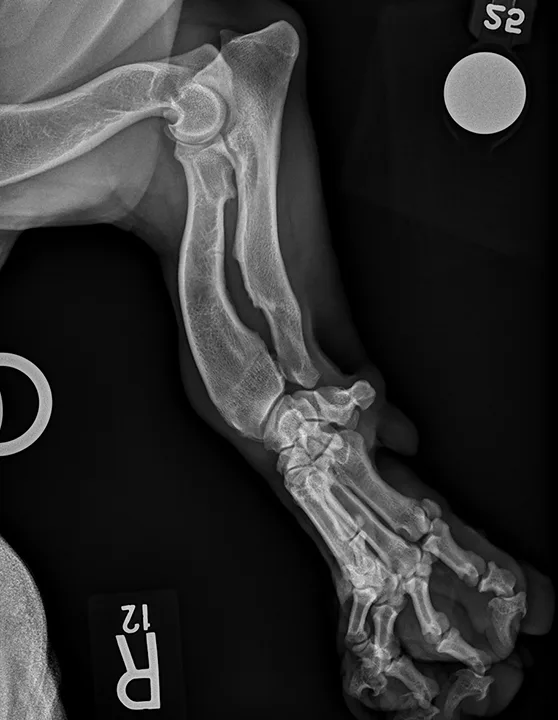

5. Musculoskeletal Variations in Chondrodystrophic & Large-Breed Dogs

Chondrodystrophic musculoskeletal variations on radiographs are generally based on the difficulty of obtaining straight lateral and craniocaudal radiographs of the thoracic limbs (Figure 6) in chondrodystrophic dogs, whereas large-breed musculoskeletal variations on radiographs are generally based on the difficulty of obtaining straight lateral radiographs of the stifles and tarsi in large-breed dogs.

Positioning chondrodystrophic dogs for musculoskeletal radiographs can be challenging because of their curved humerus, radius, and ulna. It is generally easier to position the thoracic limbs of large-breed dogs as compared with chondrodystrophic dogs, but the pelvic limbs (primarily the tarsus and stifle) may appear oblique due to the large thigh musculature on lateral projections and the inability to completely extend the coxofemoral joints. Use of pads or passive restraint (eg, ropes, tape) and/or tilting the radiographic tube can help optimize the radiographic image. Literature focused on positioning and minimizing the difficulty in interpreting normal radiographs can be found in Suggested Reading.